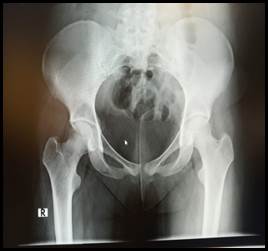

En el balance lesional primario no se constataron lesiones de órganos nobles, en tanto que a nivel osteoarticular se destaca posición viciosa a nivel de miembro inferior izquierdo en rotación externa, abducción y flexión (Figura 1), sin alteraciones a nivel de piel ni de la esfera neurovascular. Valorado en primera instancia en puerta de emergencia del Hospital de Carmelo, las radiografías iniciales (Figura 2) evidencian una luxación anterior de cadera izquierda tipo obturatriz, por lo que es enviada al Centro Hospitalario Pereira Rossell para su resolución. Al momento de arribar con 10 horas de evolución y sin cambios clínicos, se procede a reducción cerrada de la cadera en block quirúrgico bajo anestesia general, traccionando en el eje de la deformidad con cierto grado de rotación interna, logrando reducción exitosa controlada bajo intensificador de imagen y estabilidad clínica en todos sus ejes de movimiento (Figura 3). Durante el postoperatorio inmediato, se constata indemnidad neurovascular del miembro y se realiza Tomografía Computada (TC) de la cadera afecta sin evidenciar trazos de fractura, fragmentos intraarticulares ni desplazamiento epifisario (Figura 4). Con buena evolución en sala, se otorga alta a domicilio con descarga del miembro afecto por 3 semanas y control en policlínica de ortopedia infantil en 1 mes.

Figura 2:  Radiografía al ingreso